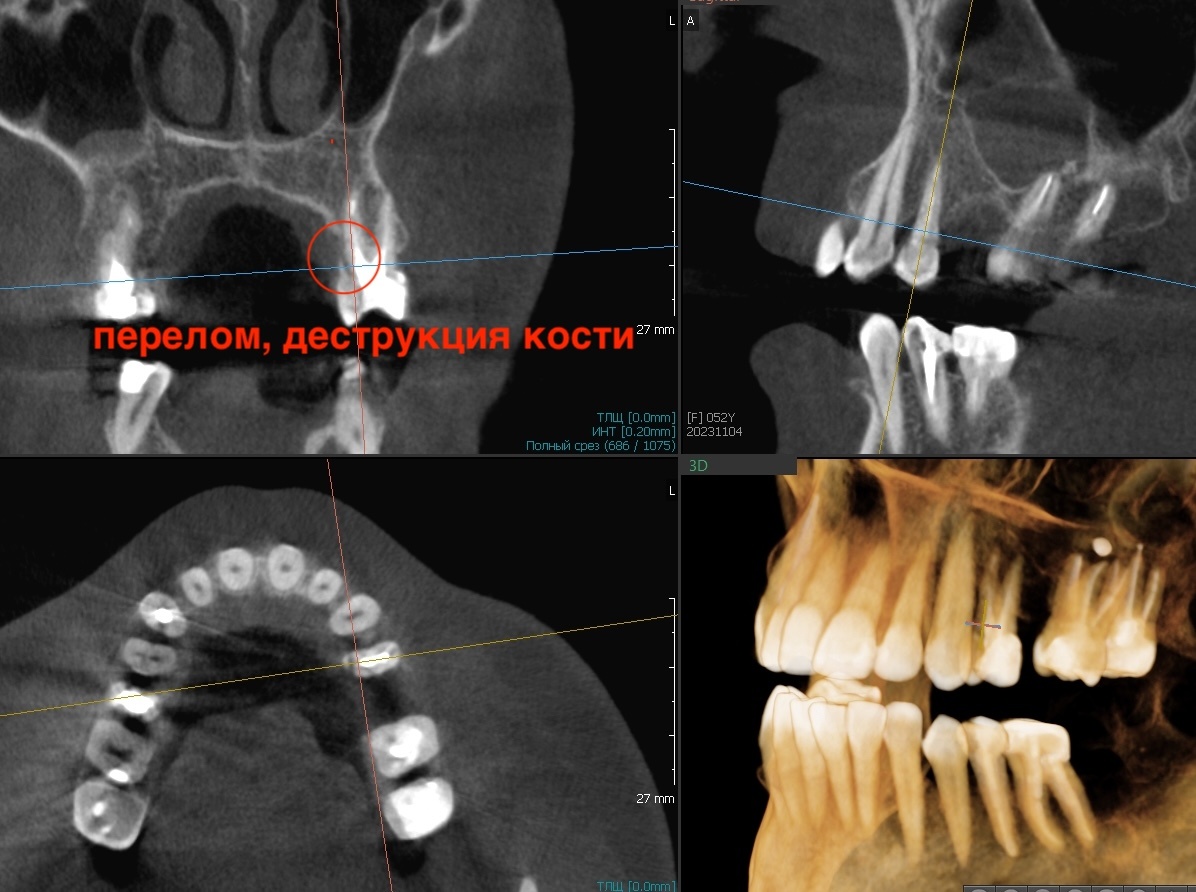

Диагностика

Четыре зуба с разрушениями под десной, кариес корней, вторичные кариесы под пломбами, периодонтиты.

Самое печальное заключается в том, что человек может даже не догадываться о масштабе проблемы. Болит редко или вообще не болит, жевать можно, внешне выглядит более-менее. А копнуть глубже - опасность на волоске. Каждый такой зуб является проблемой, которая, рано или поздно, о себе заявит громко. И полетит ситуация в крутое пике.

Вердикт суров и категоричен - четыре зуба под удаление. И это в дополнение к уже отсутствующим. По итогу нужно будет восстановить семь единиц.

В области удалённого 2.6 ситуация тоже дефицитная. Кости не хватает по высоте - до гайморовой пазухи слишком малое расстояние. А в самой пазухе на КТ видно инородное тело и присутствует.

-4

Скорее всего, пломбировочный материал от предыдущего неудачного лечения. Кто-то переусердствовал с пломбированием каналов и вывел материал в пазуху, а это чревато микозом (грибы любят инородные предметы в пазухах особенно). Отправили пациентку к ЛОР-врачу. Нельзя делать синус-лифтинг с инородным телом в пазухе.